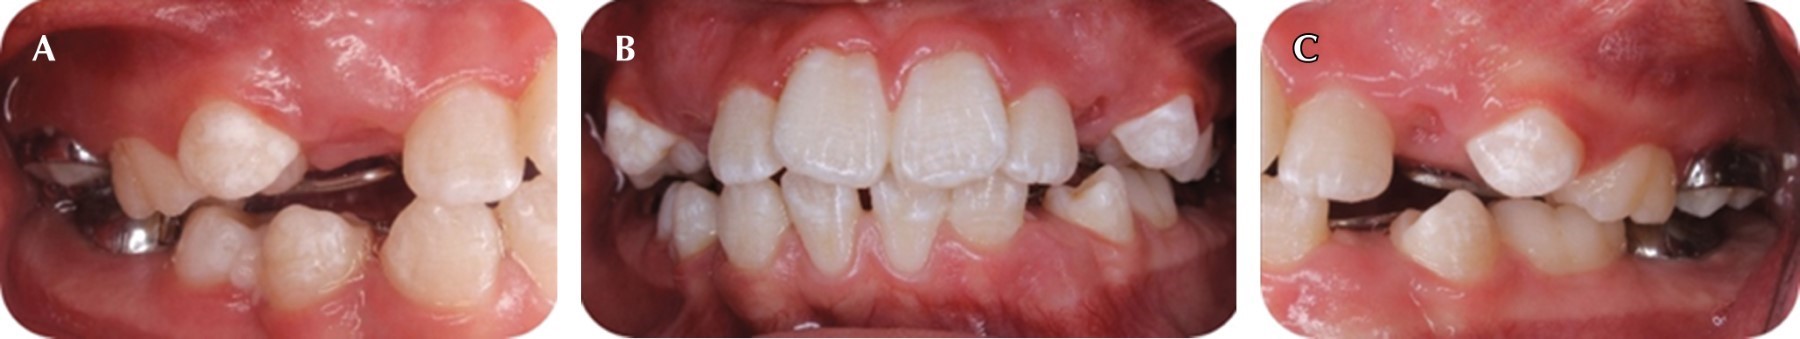

Después de 10 meses de tratamiento y buena cooperación de la paciente, tuvo una higiene bucal adecuada, en las arcadas dentales se observó una mejor conformación con un aliviamiento temporal del apiñamiento dental, relación molar clase I de Angle derecha e izquierda y relación canina indeterminable por la ausencia de caninos temporales (Figura 7). Se continuó con el uso de los aparatos por dos o tres meses más y se propuso realizar una revaloración del caso para continuar el tratamiento.

Figura 7